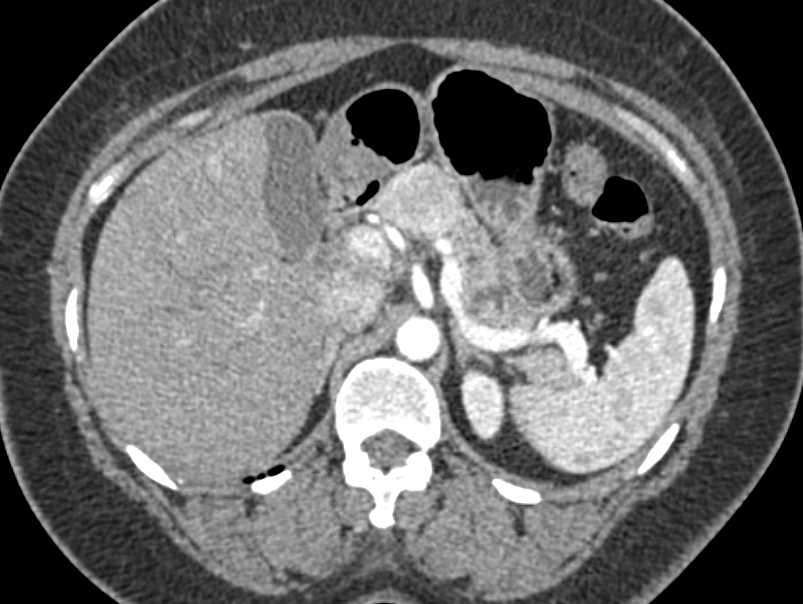

Neuroendocrine Tumor Body of Pancreas